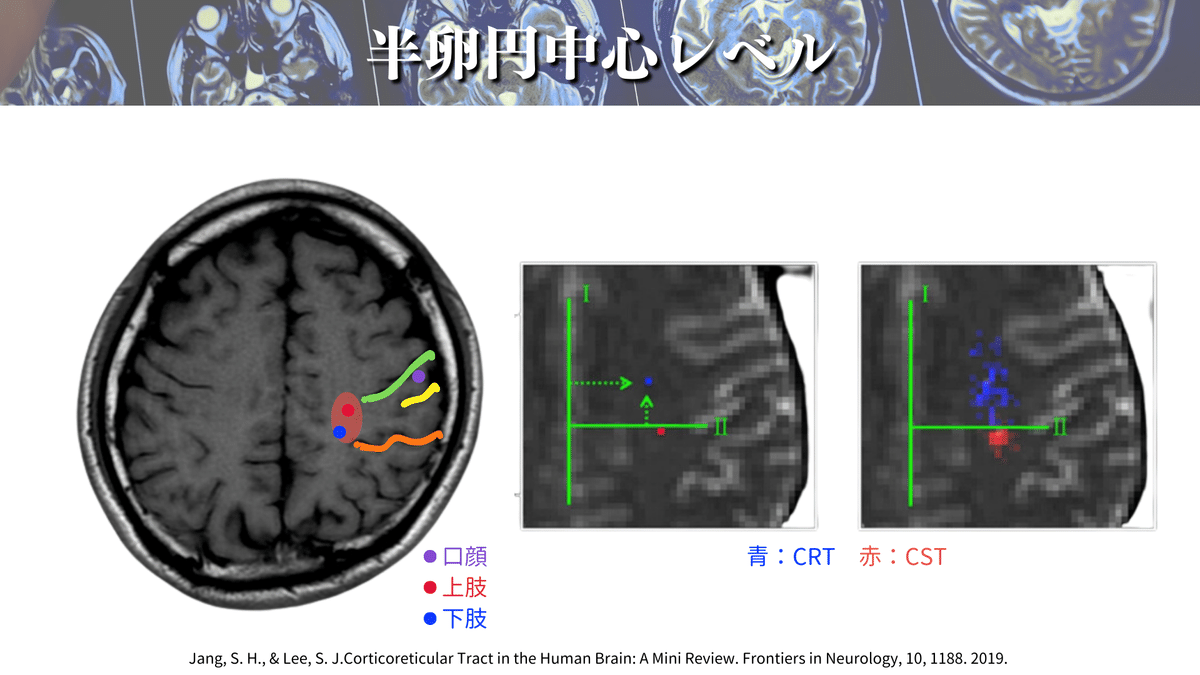

まずは大まかな場所を押さえましょう!

上図のように大体この辺りをCSTは通過していきます👍

そして、さらに解像度を上げると、、、🔍

こんな感じになります!(上図)

このレベルでは口顔👄の効果器特異的領域も見えてくるかもしれません!

Q:口顔はCSTではないの?

はい。実は口顔の運動線維は厳密にいうとCST(皮質脊髄路)とは別の「皮質延髄路(皮質核路)」という線維が担っています!

これは名前から理解するのが一番わかりやすいかと思いますが、CSTは皮質から脊髄の下位運動ニューロンまで投射するので「皮質脊髄路」という名前がついていますよね☝️

口や顔の場合は反対側の顔面神経や舌下神経などの脳神経核に投射することになります!

もうお気づきかと思いますが、脳神経核は橋や延髄にあり、最も遠い場所を名前に入れるので「皮質延髄路」、または、脳神経核まで投射するので「皮質核路」という名前がついているわけですね✨

ですので、厳密にいうとCSTと皮質延髄路は別の神経線維ということになります!

ただ、内包レベルよりも頭側ではほぼ同じ経路を通るので安心してくださいね👍

上肢や下肢の配置はおおよそ図のようになっていますよ🖐️🦶